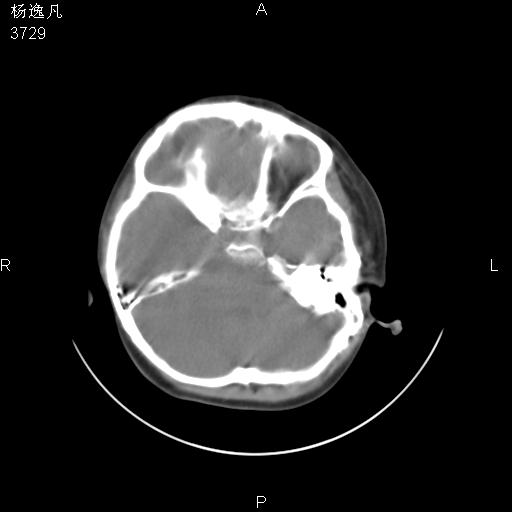

男性,5岁,面部受外伤,余无特殊

薄层

1、右面部及颞部软组织肿胀。

2、腺样体肥大。

头颅ct平扫未见明确外伤性征象,右侧面部及颞部软组织肿胀,后鼻腔软组织影增大,增厚,鼻咽顶部变窄,考虑鼻咽腺样体增值肥厚。